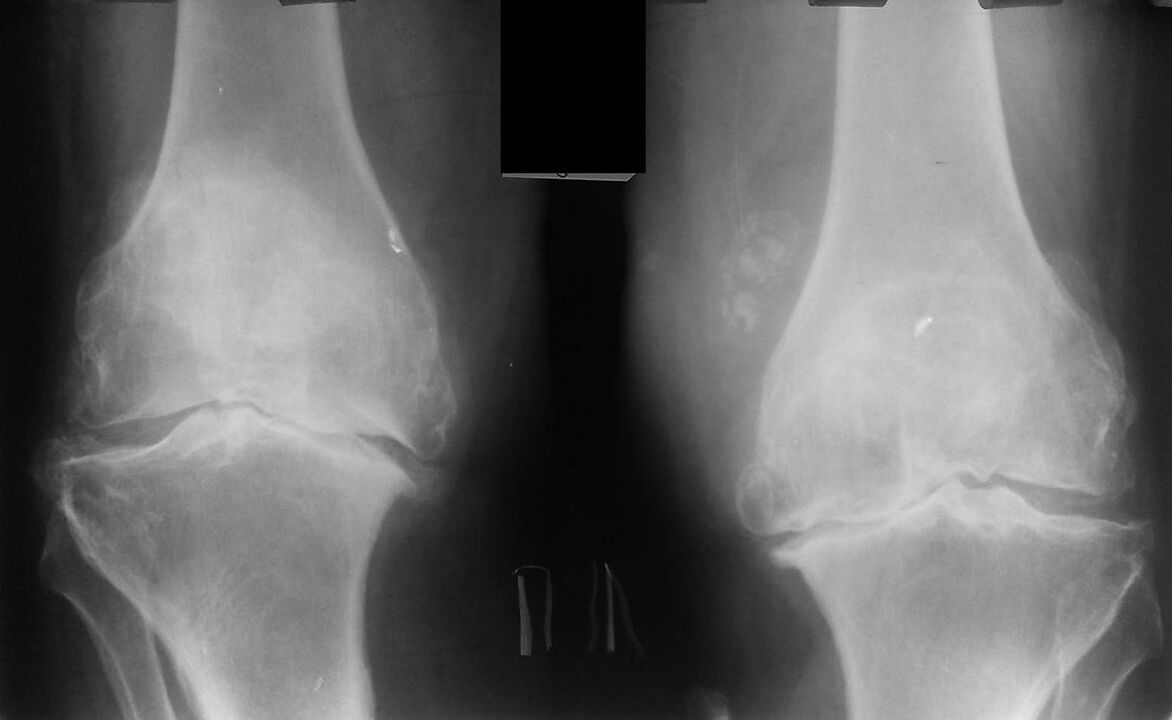

An X-ray is a standard research method that allows the diagnosis to be confirmed, the extent of abnormalities to be determined, the dynamics of the process to be monitored, and other pathological processes (such as tumors) in the tibia and femur to be ruled out. .

It should be noted that primary changes in the structure of the knee joint may be absent on radiographs. The narrowing of the joint gap and the compaction of the subchondral zone are then determined. The joint ends of the femur, and especially the tibia, dilate, and the edges of the condils become pointed.

- The second stage is characterized by more acute pain that does not stop with immobility of the limb. A crack is displayed. Fluid accumulates in the joint cavity, and the X-ray shows deformation and growth of the bone. At this stage, the patient tries in every possible way not to move the affected limb. Your doctor will prescribe injections and chondroprotectors - medicines that help cartilage to recover.

- In the last third stage, the pain becomes permanent and often worsens as the weather conditions change. X-ray shows significant deformity of the knee, which can only be corrected by surgery, the patient must take a complex of chondroprotectors. The patient's gait changes: he walks on half-bent legs or rolls from side to side.